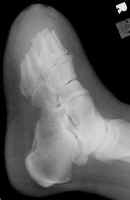

The images above demonstrate a transmetatarsal amputation through all five digits.

The bone edges are beveled and there is a generous soft tissue pad.

Another transmetatarsal amputation.